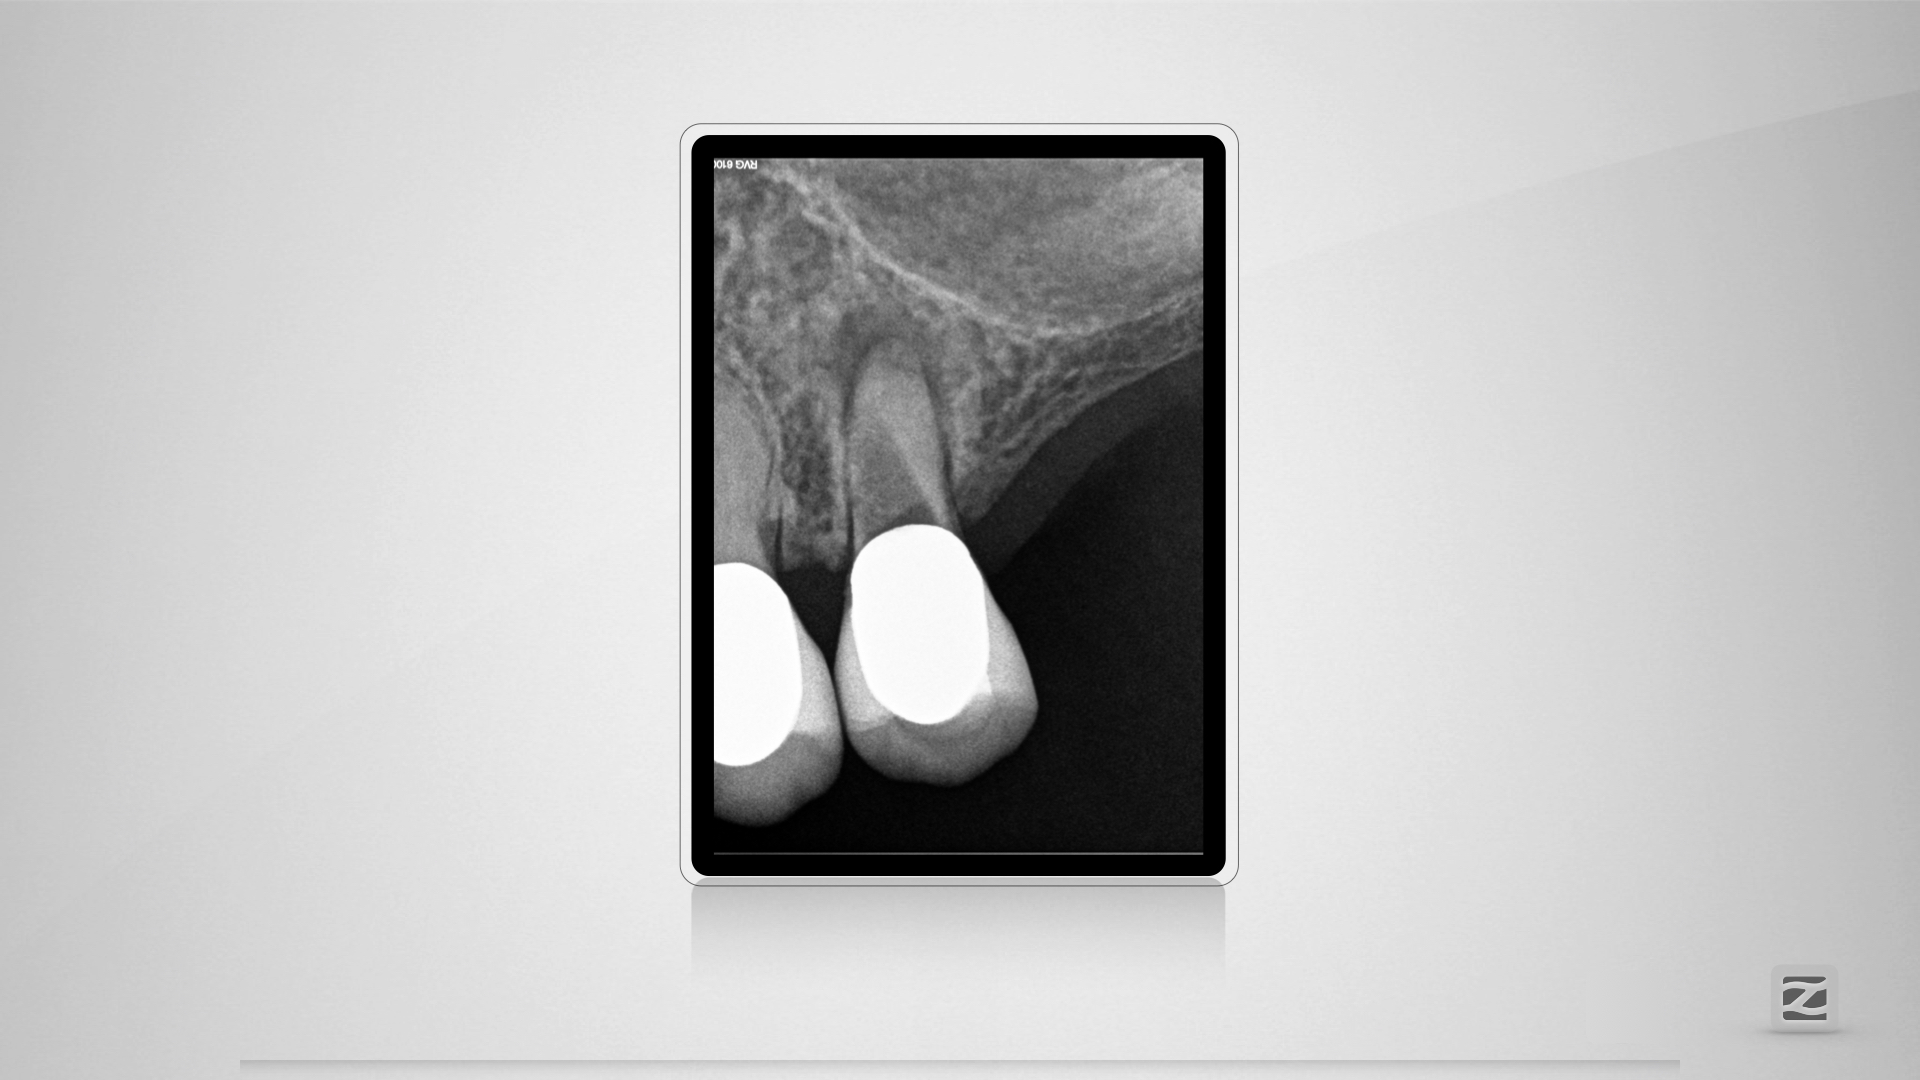

PerforationD.004

Übermut tut selten gut.